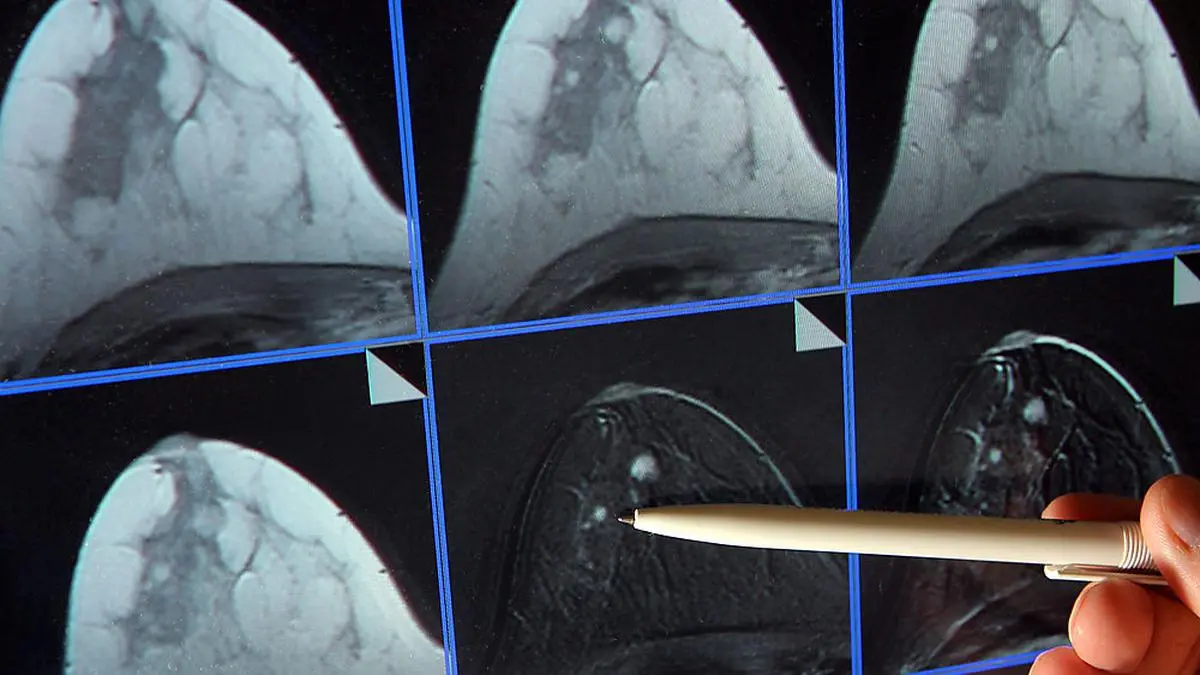

Am 1. Kärntner Krebstag sind Interessierte eingeladen, sich im Klinikum Klagenfurt über das Thema Krebs zu informieren. Geboten werden Vorträge und Beratung, Diskussion und begehbare Organmodelle.

Krebs wird immer früher erkannt